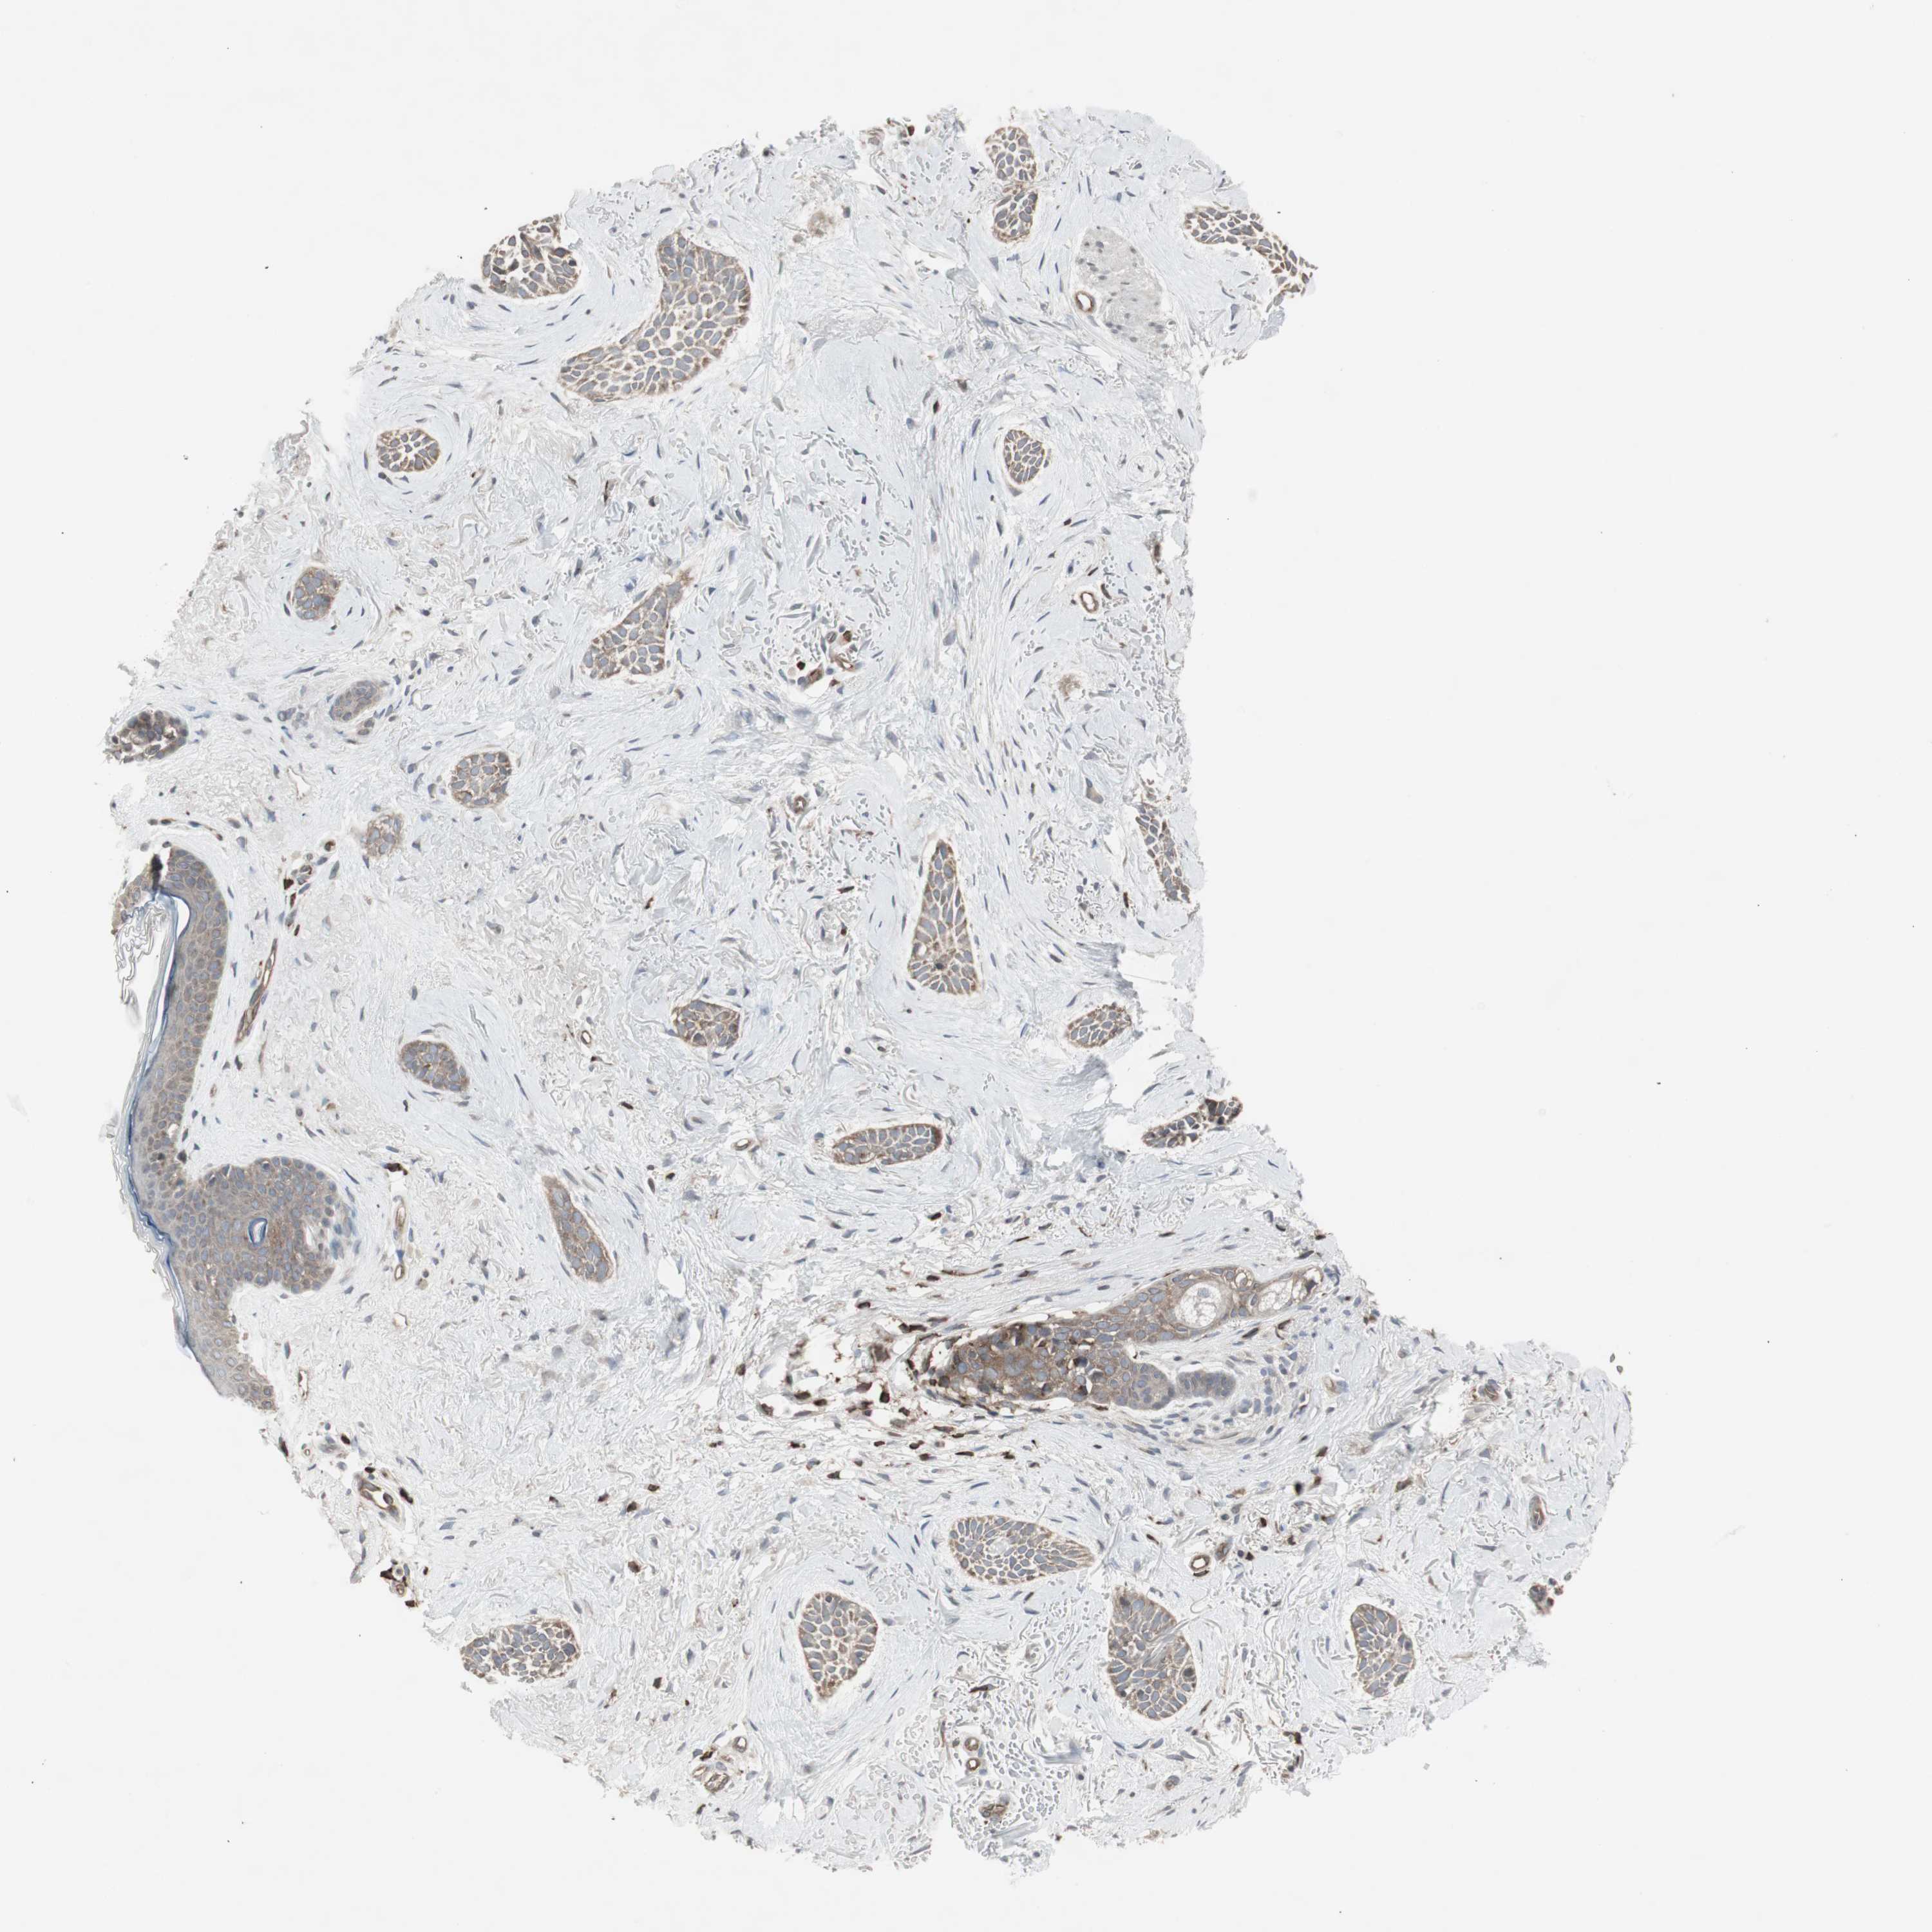

SKIN CANCER - Protein expressioni

A mouse-over function shows sample information and annotation data. Click on an image to view it in a full screen mode. Samples can be filtered based on level of antibody staining by selecting one or several of the following categories: high, medium, low and not detected. The assay and annotation is described here.

Each image is clickable and will lead to virtual microscopy that enables deeper exploration of all samples and also displays staining intensity scores, fraction scores and subcellular localization as well as patient and tissue information for each sample.

Antibody CAB009502

Adnexal tumor, benign